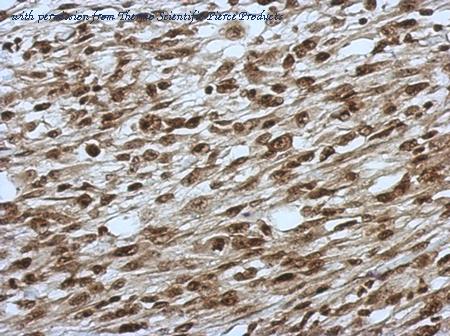

- Slu7 antibody